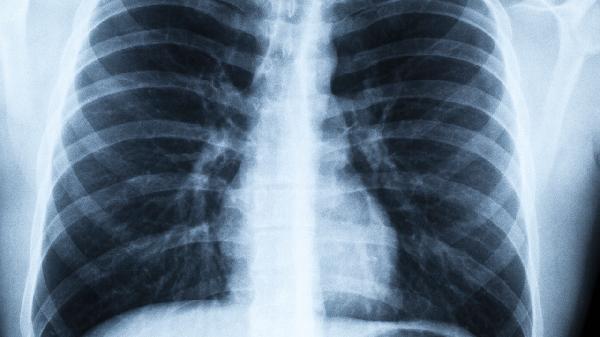

建议进行血氧检测和胸部影像学检查,排除潜在问题。